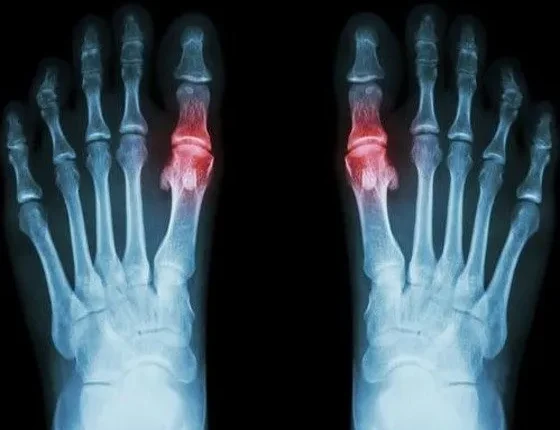

Η ουρική αρθρίτιδα, η οποία συνήθως επηρεάζει τη μεγάλη άρθρωση του μεγάλου δακτύλου, αλλά μπορεί επίσης να εμφανιστεί στους αστραγάλους, τα δάχτυλα των χεριών, τους καρπούς, τα γόνατα ή τους αγκώνες, οφείλεται στην ανικανότητα του σώματος να ελέγχει τα επίπεδα του ουρικού οξέος. Καθώς τα επίπεδα του ουρικού οξέος αυξάνονται, σχηματίζονται κρύσταλλοι που συλλέγονται στη βάση της άρθρωσης του μεγάλου ποδιού, δημιουργώντας φλεγμονή και πόνο.